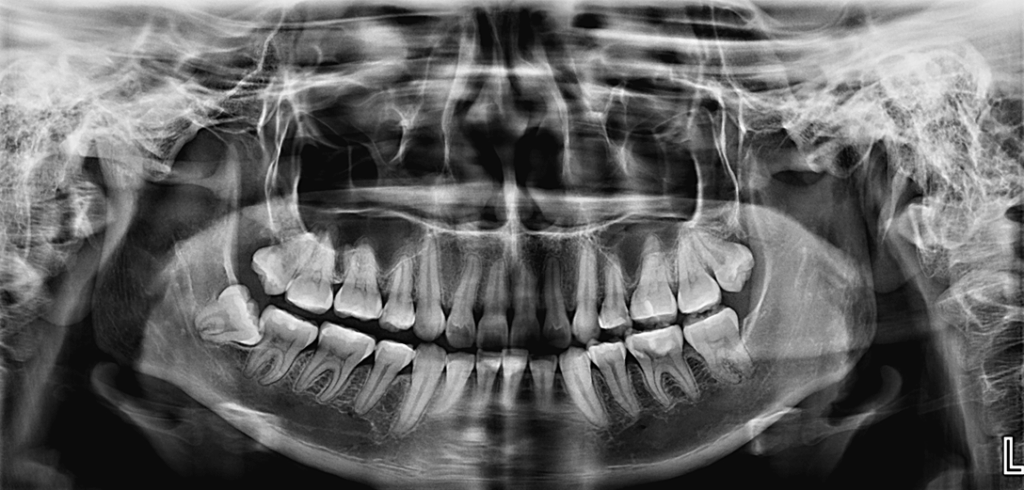

Paciente femenina de 20 años acude al centro para una evaluación imagenológica de ATM, a la evaluación de la radiografía panorámica se observa el aplanamiento del contorno condilar del lado derecho y la aparente alteración de la morfología condilar del lado izquierdo, asimismo se observa la neumatización de ambos senos maxilares a predominio del lado izquierdo, lesión cariosa distal

de la pieza 25, múltiples restauraciones coronarias y la impactación de la pieza 48.

Radiografia Panorámica

Los principales signos hallados por medio del diagnóstico por imágenes son: esclerosis del hueso subcondral, erosión, aplanamiento de las superficies articulares, deformación en la superficie condilar, osteofitos y disminución del espacio articular 9,32,50 . La radiografía panorámica, es la primera herramienta para identificar cambios estructurales a nivel de la ATM; sin embargo, la agudeza con la que puede evidenciar estos cambios debe ser evaluada con Cuidado.